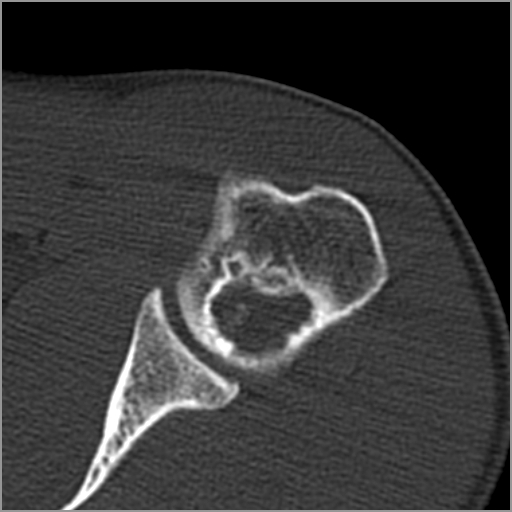

以下是引用zxd95在2008-7-19 18:45:00的发言:[br]囊性病灶边缘硬化、皮质变薄但连续——提示生长时间长、良性病变——考虑左肱骨头骨囊肿。[br]

以下是引用杀毒软件在2008-7-19 18:55:00的发言:[br]考虑:骨巨细胞瘤可能性大